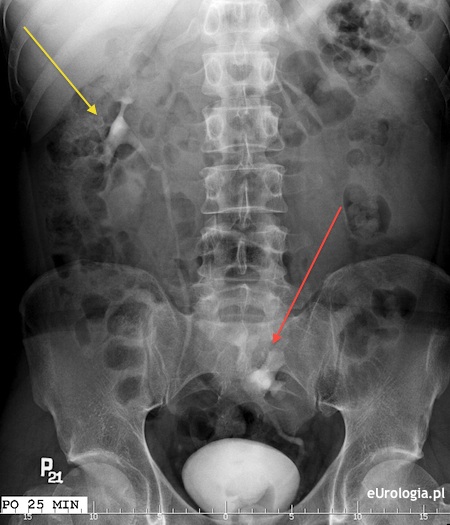

Fot. Urografia pacjenta z ektopową lewą nerką. Lewa nerka położona w miednicy małej.